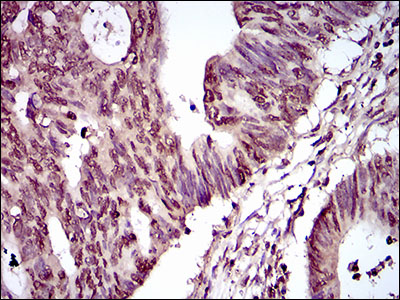

Immunohistochemical analysis of paraffin-embedded ovarian cancer tissues using PIWIL4 mouse mAb with DAB staining.

Immunohistochemical analysis of paraffin-embedded rectum cancer tissues using PIWIL4 mouse mAb with DAB staining.